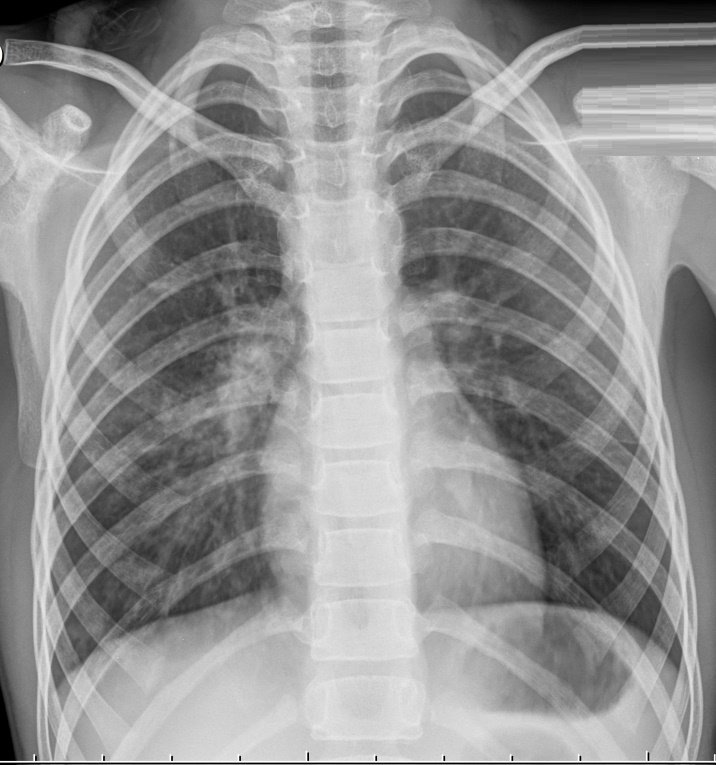

Рентген снимок атипичной пневмонии

Атипичная пневмония — собирательный термин, включающий инфекционно-воспалительные поражения тканей лёгких. Причинами являются нехарактерные возбудители — микоплазма, хламидия, легионелла, вирусы. Воспаление лёгких протекает с повышением температуры, одышкой, общим недомоганием.

Диагностировать патологический процесс можно при помощи рентгена. Так, для микоплазменной формы характерна неоднородная инфильтрация лёгочной ткани, она может определяться слабо или быть среднеинтенсивной.

При легионеллезной, на снимке видно уплотнения (инфильтраты) округлой формы, локализующиеся на поверхности одной доли лёгкого. В ряде случаев наблюдается слияние инфильтратов.

У 25% пациентов одновременно с пневмонией определяется плеврит, с незначительным скоплением секрета в плевральной полости.

Правосторонняя бронхо- пневмония

Практически невозможно отличить пневмонию Legionella от других, основываясь на таком методе обследования. Присутствие легионеллы или хламидии подтверждается серологическим анализом крови.